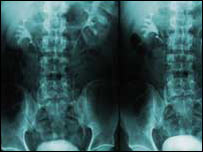

脊柱分裂

脊柱分裂是一种严重的先天性疾病